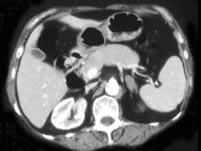

问题 女,42岁,夜尿增多伴高血压,实验室检查:血和尿醛固酮水平增加,请结合图像,选择最佳答案 ( )

选项 A、双侧肾上腺转移瘤 B、双侧肾上腺淋巴瘤 C、双侧肾上腺腺瘤 D、双侧肾上腺未见异常 E、双侧肾上腺增生

答案 E